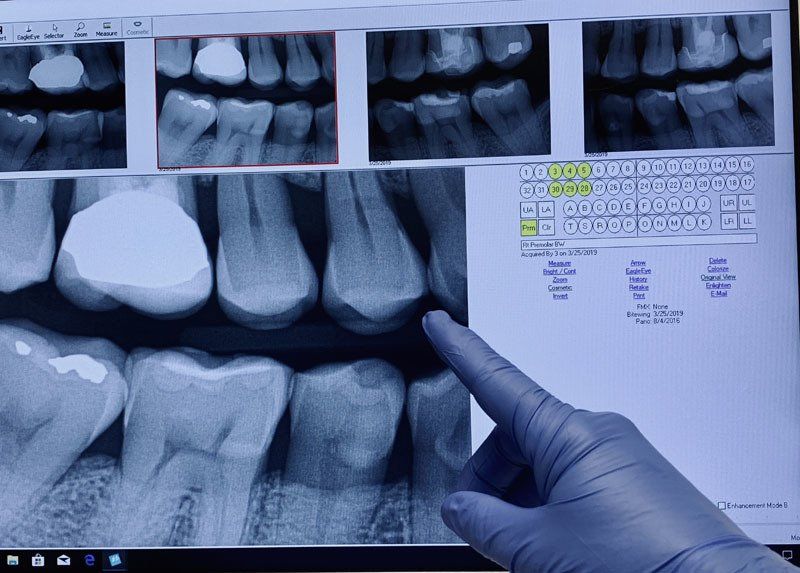

DENTAL X-RAY

Dental X-rays have come a long way. Today, dental X-rays are safer, faster, more comfortable and more informative than in years past. Digital X-rays, one of the latest and most advanced dental technologies, produce high-quality images of your teeth that can be viewed instantly by you and your dentist on an LCD monitor. Digital X-rays reduce radiation by up to 90% and provide exceptional diagnostic information to ensure that potential problems are caught in their earliest stages. Intraoral photography is another alternative to traditional dental X-rays. With intraoral photography, problems such as cavities, fractures and discolorations in the teeth are captured through clear and sharp photographic images.